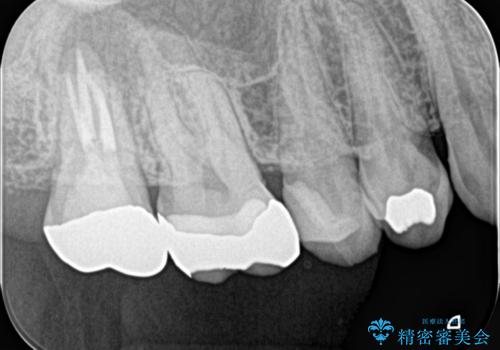

レントゲンと,CT撮影を行なったところ右上小臼歯が虫歯、右上第二大臼歯には根の先に大きな病気がありました。

セラミックインレーは古い材料を拡大鏡でしっかり取り除き適合の良い詰め物が装着されました。